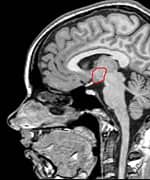

By sheer serendipity, many years ago Dr. Gordon provided care for a young man with a history of numerous sports-related head injuries, whose parents were themselves patients at the clinic. The young man's symptoms long outlasted the immediate effects of his acute injury and included loss of concentration, memory, mental energy, focus, and physical well-being, often accompanied by loss of lean muscle mass and an increase in body fat. The parents, familiar with the effects of hormonal imbalances, naturally assumed that their son's problems might reflect an endocrine problem of his own. And indeed, many of his symptoms resembled those of adult patients with so-called hypopituitarism, or loss of pituitary gland function. The pituitary gland is located at the base of the brain and is sometimes called the "master" gland of the endocrine system, because it controls the functions of the other hormone- secreting glands. Gordon, who is nothing if not intellectually curious, hit the books. What he found was startling and life-changing, for himself as a clinician, for his young patient, and now for scores of additional victims of traumatic brain injury. Symptoms of Traumatic Brain Injury Mimic Pituitary DysfunctionDr. Gordon found a wealth of published literature suggesting that traumatic brain injury causes pituitary dysfunction, confirming his initial hunch.1 Although the figures vary between studies, at least 50% (and up to 76%) of traumatic brain injury victims show some loss of pituitary hormone function immediately after the brain injury.2-4 In general, the more severe the original brain injury, the more profound the hormonal deficits, although hormone deficiency or insufficiency (levels in the low "normal" range) are seen even in patients with mild traumatic brain injury.5-9 And while about 58% of patients recover their normal pituitary function within one year of their head injury, a shocking 52% develop new pituitary hormone deficiencies after one year. 10,11 Those deficits include reductions in many different pituitary hormones, including those that regulate the thyroid gland, the adrenal glands (that produce cortisol, DHEA, and other vital hormones), the gonads (where estrogen and testosterone are produced), and growth hormone.3,4,12,13 The severity of the hormone deficiencies correlates strongly with the kinds of symptoms Dr. Gordon was seeing in his patient. For example, patients with growth hormone deficiency or insufficiency had significantly worse disability rating scores, greater rates of depression, worse quality of life, lower energy, greater fatigue, and poorer emotional well-being, compared to brain injury patients with normal hormonal levels.14,15 Dr. Gordon's hunch was borne out: patients with traumatic brain injury often have pituitary hormone deficiencies or insufficiencies, especially in growth hormone. And those defects are closely associated with the persistent neurological, psychological, and emotional deficits that are so tragically common in survivors of traumatic brain injury. And where are you most likely to find a high concentration of survivors of traumatic brain injury? The United States military.

Growth Hormone: A Critical PlayerGrowth hormone is the most common hormone deficiency or insufficiency in patients with traumatic brain injury at any level of severity.16-19 Deficiencies in this hormone are especially marked in patients with moderate to severe traumatic brain injury.20 Brain-injured patients with growth hormone deficiency experience rapid weight gain and have substantially lower levels of other hormones as well.17,19 Low growth hormone levels are also associated with excessive anxiety and depression and poor physical health and quality of life.15,21 Finally, brain-injured patients with growth hormone deficiency show greater deficits in attention, executive functioning, memory, and emotion than those with normal growth hormone levels.22 Growth hormone is an intriguing hormone, and we are learning more about it each year. In children, it is responsible for regulating linear growth, ultimately determining adult height and body proportions. But growth hormone has many other remarkable functions throughout the body and into adulthood. It is neuroprotective, increasing survival of damaged nerve cells and promoting regeneration of nerve tissue.23-25 Growth hormone also increases the number of receptors for other hormones in tissues throughout the body; this has the effect of increasing the body's sensitivity to those hormones' actions, helping to overcome the effects of their deficiencies.26-29 Like all hormones, growth hormone acts by binding to specific cell-surface receptors. Receptors for growth hormone are found throughout the brain, and they are especially densely distributed in brain regions responsible for learning and memory.30,31 That may explain why declining growth hormone levels are associated with poorer cognitive function. Growth hormone levels fall with age and are especially low in Alzheimer's disease.32-36 As Dr. Gordon points out, it is therefore not surprising that traumatic brain injury patients often show symptoms identical to the cognitive decline and memory loss we see with aging and Alzheimer's disease. In essence, a brain-injured patient with low growth hormone levels undergoes accelerated cognitive aging. Hope for Traumatic Brain Injury Patients at Millennium Health Centers